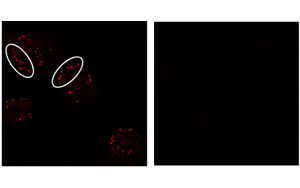

Cancer Cell發現了一些癌癥對免疫治療沒有反應的關鍵原因:代謝機制阻礙免疫反應

密歇根大學Rogel癌癥中心的研究人員發現了一些癌癥對免疫治療沒有反應的關鍵原因:腫瘤微環境中的代謝物轉運體阻斷了免疫反應不可或缺的一種關鍵類型的腫瘤細胞死亡。